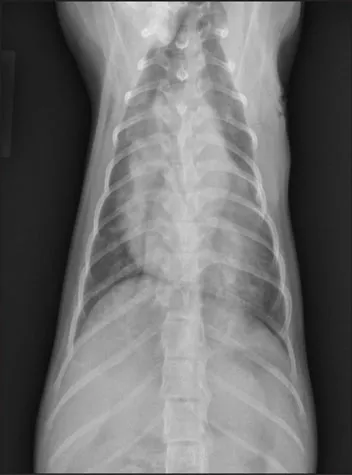

CASE 1.1 A 7-year-old neutered male Labrador Retriever who was hit by a car. You obtain these thoracic radiographs: Figs. 1.1a, b, left and right lateral projections, respectively; Figs. 1.1c, d, ventrodorsal and dorsoventral projections, respectively.

1.1d